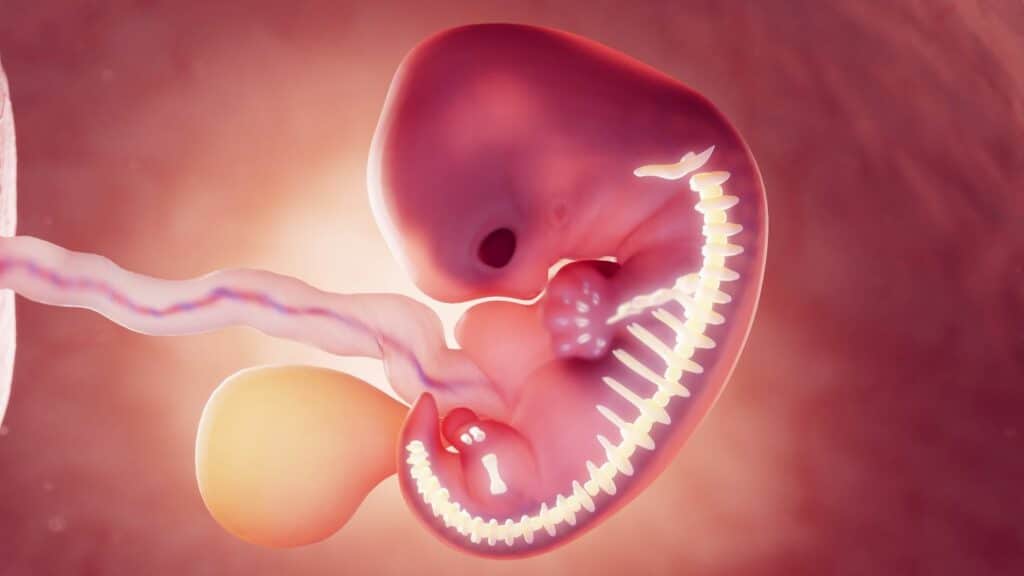

Die Plazenta entwickelt sich im Laufe Deiner 8. Schwangerschaftswoche. Ab dann kann ein Embryo auch als Fötus bezeichnet werden, da sich die Organe ausbilden und weiterentwickeln.

Sie fängt dann an, kleine Zotten zu bilden, die die Blutgefäße des Embryos bilden. Diese wachsen bis in die Gebärmutterwand und Nabelschnur.

Während Dein Baby munter vor sich hin wächst, bildet sich eine feine Membran. Diese ermöglicht nicht nur den Stoffaustausch, sondern schützt den Fötus auch vor Deinem Immunsystem. So ist Dein Kind rundum geschützt und kann beruhigt mit seiner Entwicklung beginnen.

Ab der 18. bis 20. Schwangerschaftswoche ist die Plazenta dann voll ausgebildet. Ab dann hört sie allerdings nicht mit wachsen auf, sondern wächst die komplette Schwangerschaft mit.